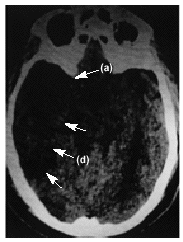

Figura 1.

Paciente varón, de 70 años, con antecedentes de miocardiopatía dilatada en fibrilación auricular crónica. Se presenta con un cuadro brusco de pérdida de conciencia con hemiparesia derecha; posteriormente, se constata también hemiparesia del lado izquierdo.

En la figura 1 se aprecia hipodensidad en la región protuberancial izquierda y en hemisferios cerebelosos que comprimen la parte posterior de la cisterna protuberancial. En la figura 2 se observa una hiperdensidad en la salida de la arteria cerebral media (ACM) derecha (a) e hipodensidad de su territorio tributario, y en la figura 3 una hipodensidad de todo el territorio de la ACM derecha. Las flechas de la imagen delimitan la zona isquémica y señalan la hiperdensidad de la ACM, posición M1.

Diagnóstico: infarto de la protuberancia (b), cerebeloso (c) y del territorio de la ACM derecha (d) con visualización de la oclusión de la arteria tributaria de origen embólico.